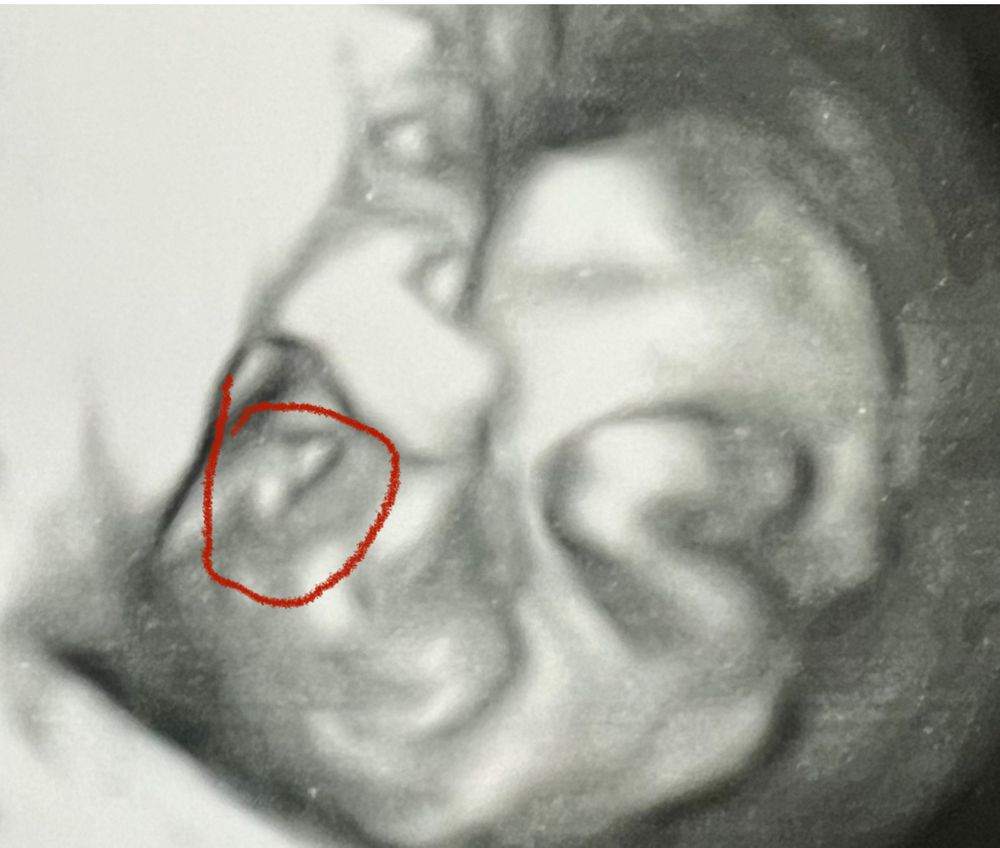

Сходила на узи. Там всё в полном порядке.

Мирончик лицо показывать не хочет, зато мужское достоинство мне узист показала отчетливо.🤣 Знакомая до боли картина…